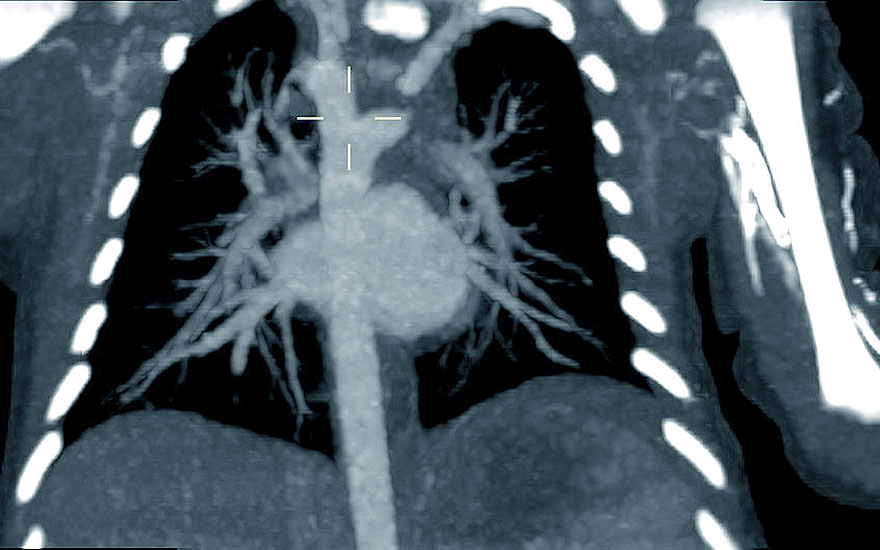

El Servicio de Diagnóstico por la imagen del Hospital Universitario Quirónsalud Madrid ha realizado una tomografía computarizada (TC) de ultrabaja radiación a un bebé de dos días de vida para confirmar la presencia de un doble arco aórtico. "Esta patología se da en recién nacidos que no sólo tienen un cayado aórtico, sino dos. En estos casos el cayado derecho suele ser el dominante", explica la doctora Ana Álvarez

, del Servicio de Diagnóstico por la Imagen.

La detección de este caso se realizó intraútero; sin embargo, una vez nacido, el pequeño fue sometido a esta prueba para tener una visión más precisa de la lesión para planificar una cirugía. "Estos bebés sufren un riesgo de estenosis de la vía aérea ó digestiva y pudiendo presentar tos recurrente, neumonías de repetición y problemas para tragar que sería necesario corregir quirúrgicamente".

¿Cómo se realiza un TC a un bebé? La doctora Álvarez aclara que esta prueba en principio no está indicada para niños, pero que gracias a los equipos de ultrabaja radiación y los protocolos específicos para niños que adaptan la realización de la prueba al peso y al tamaño del bebé es posible realizar esta prueba ajustando siempre al máximo la zona de visualización para reducir la radiación que recibe el bebe. "La inyección del contraste era necesaria para observar el arco aórtico con precisión. En el caso del bebé se realizó manualmente con jeringa ajustando los requerimientos de contraste al estudio tan breve que se llevó a cabo". En este caso se utilizó contraste yodado ayustado al peso del paciente (6 cc.).

"Las tomografías computerizadas en bebés no son muy comunes, pero sobre todo se realizan para analizar malformaciones congénitas cardiovasculares o problemas en el cierre craneal en bebés (craneosinostosis). Los equipos como los que dispone Quirónsalud Madrid son untrarrápidos y de ultra baja radiación y permiten llevar a cabo la prueba en apenas 30 décimas de segundo. El estudio se realizó con sincronización cardiaca que permite la adquisición de la imagen en un momento determinado del ciclo cardiaco del recién nacido.

Imagen de tomografía computarizada del corazón y del doble arco aórtico del bebé.